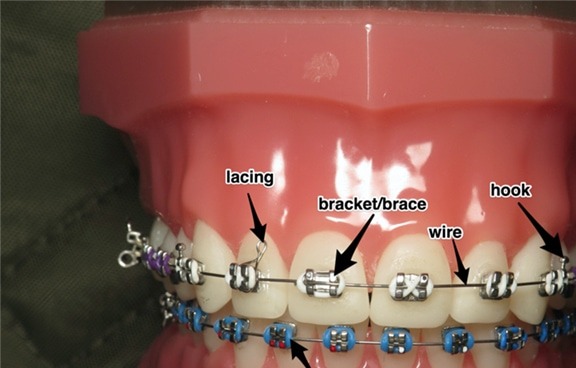

The Components of Your Appliance

Before managing an emergency, it helps to know the parts of your orthodontic appliance:

- Brackets the small pieces bonded to each tooth

- Wire (archwire) the metal wire connecting the brackets and guiding tooth movement

- Ligatures the small elastics or metal ties that attach the wire to the bracket

- Intermaxillary elastics the rubber bands you hook between the upper and lower arches

- Molar tubes the attachments on the back teeth where the wire is inserted

- Powerchain (elastic chain) a chain of small rings used to close gaps

Identifying the problematic piece will help you better describe the situation to our team.